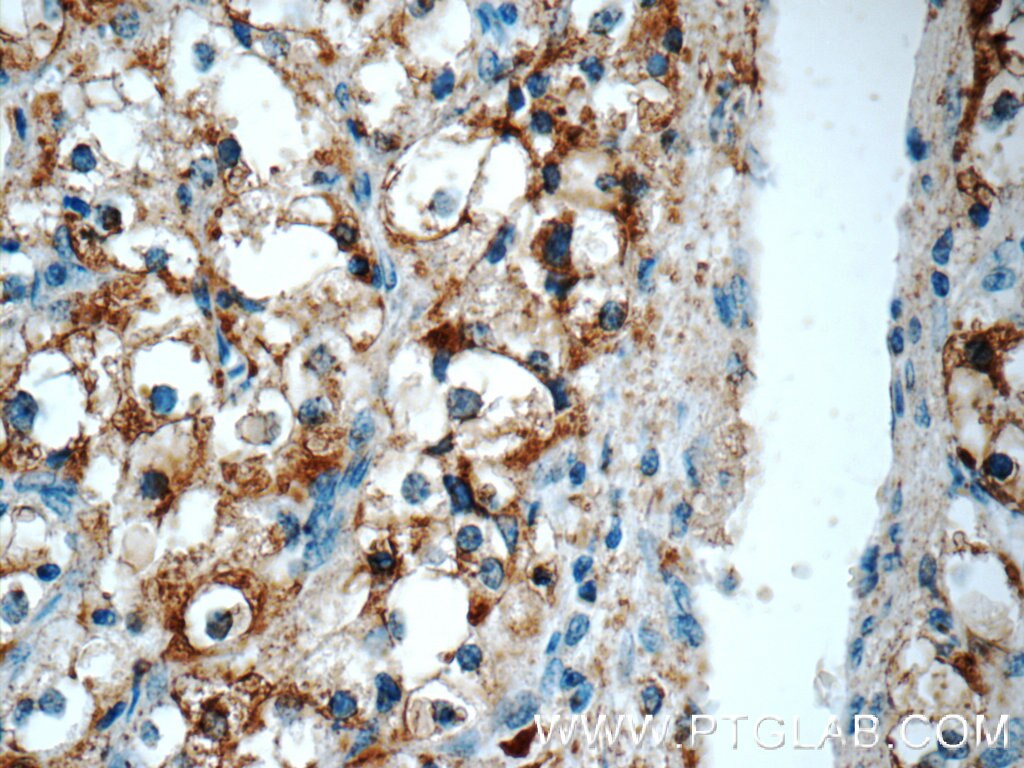

Amacr P504s Antibody 15918 1 Ap Proteintech

Amacr P504s Antibody 15918 1 Ap Proteintech from www.ptglab.com